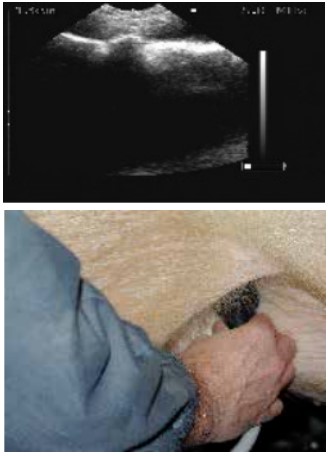

扫描配种第24天的母猪,大的胚胎囊可以很容易的看到。

Scans day 24. Large embryos bladders which are easy to see.

位置3的超声波图像.

ltrasound image position 3.

扫描仪的探头涂上耦合剂后置于腹股沟部。

The scanner head is applied gel and is placed in the groin.

缓慢地移动探头,直至出现胚胎清晰的图像。

lowly move the scanner head around until there is a clear picture of the fetus.